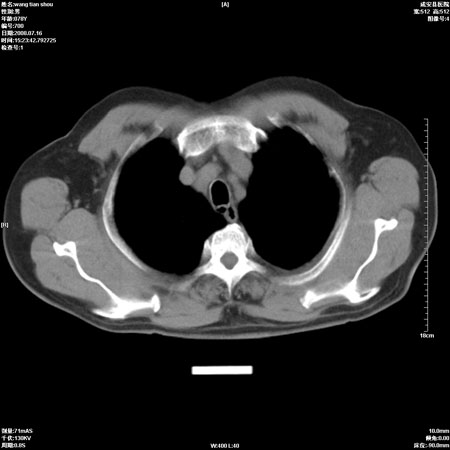

以下是引用qingjing在2008-7-16 19:55:00的发言:[br]1、左上肺不张并堵塞性炎症,建议支气管镜详查;[br]2、左侧胸腔少量积液。

以下是引用wzr在2008-7-16 20:26:00的发言:[br]左肺肺不张伴阻塞性肺炎!另:左侧胸腔少量积液。建议纤支镜检查!